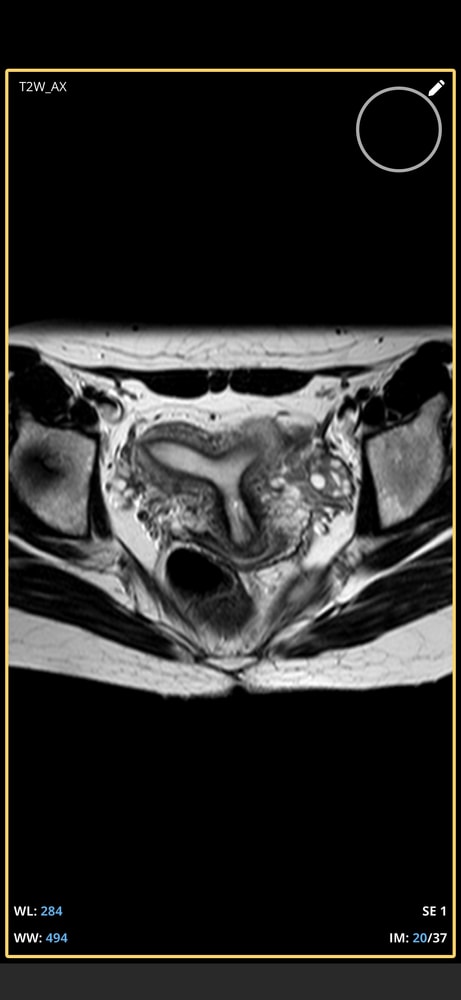

Тоже подумала про седловидную)

Нужны более тонкие срезы и все исследование, чтоб посмотреть нет ли перегородки.

Таро Расклады на зачатие , одни врачи говорят двурогая, другой врач утверждает, что т образная